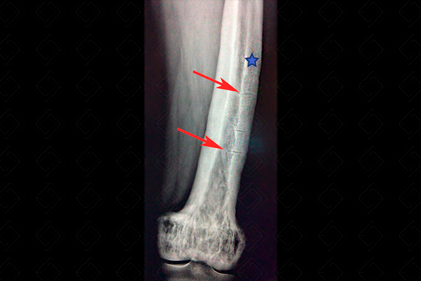

Texto alternativo para a imagem Figura 1. Créditos: Dra. Elazir Mota - Rio de Janeiro/RJ

Descrição da figura 1: Radiografia do fêmur em paciente portador de doença de Paget. Observar o trabeculado ósseo grosseiro na região metadiafisária, o espessamento cortical (asterisco) e as fraturas em banana – fraturas horizontais (setas vermelhas).

A doença de Paget pode ser dividida em três fases radiológicas: lítica , na qual predomina a reabsorção óssea pelos osteoclastos, mista e sua fase final , blástica.

• Na fase final ou blástica, observam-se áreas de esclerose e aumento do volume ósseo. Nesta última fase da doença, devido à excessiva deposição de osso "anormal", há uma grande predisposição a fraturas, como as características fraturas em banana (figuras 1 e 2). As múltiplas fraturas e o remodelamento ósseo anormal acarretam nas deformidades ósseas. Na calota craniana, há espessamento da tábua interna, levando ao aumento do espaço diploico ( Tam O`Shanter - boina escocesa), podendo acarretar em sintomas neurológicos. Na coluna, o excessivo remodelamento leva ao surgimento da vértebra em marfim , podendo haver aumento volumétrico do corpo vertebral e seus elementos posteriores.